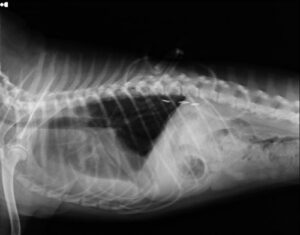

術前レントゲン

胸水が呼吸困難を生じさせるレベルに貯留していました。術前に胸管の走行を知るために膝窩リンパ節造影を試みましたが胸管を造影することはできませんでした。

再発時のレントゲンです。クリップが外れているなどの所見はありませんでした